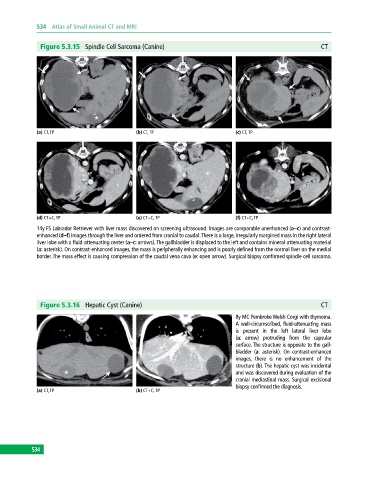

Figure 5.3.15 Spindle Cell Sarcoma (Canine) CT

(a) CT, TP (b) CT, TP (c) CT, TP

(d) CT+C, TP (e) CT+C, TP (f) CT+C, TP

14y FS Labrador Retriever with liver mass discovered on screening ultrasound. Images are comparable unenhanced (a–c) and contrast‐

enhanced (d–f) images through the liver and ordered from cranial to caudal. There is a large, irregularly margined mass in the right lateral

liver lobe with a fluid‐attenuating center (a–c: arrows). The gallbladder is displaced to the left and contains mineral‐attenuating material

(a: asterisk). On contrast-enhanced images, the mass is peripherally enhancing and is poorly defined from the normal liver on the medial

border. The mass effect is causing compression of the caudal vena cava (e: open arrow). Surgical biopsy confirmed spindle cell sarcoma.

Figure 5.3.16 Hepatic Cyst (Canine) CT

8y MC Pembroke Welsh Corgi with thymoma.

A well‐circumscribed, fluid‐attenuating mass

is present in the left lateral liver lobe

(a: arrow) protruding from the capsular

surface. The structure is opposite to the gall-

bladder (a: asterisk). On contrast‐enhanced

images, there is no enhancement of the

structure (b). The hepatic cyst was incidental

and was discovered during evaluation of the

cranial mediastinal mass. Surgical excisional

biopsy confirmed the diagnosis.

(a) CT, TP (b) CT+C, TP